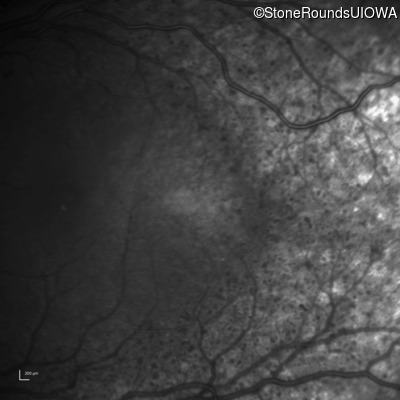

Swept-Source OCT - Left - 20/40 +2 sc

Exemplar